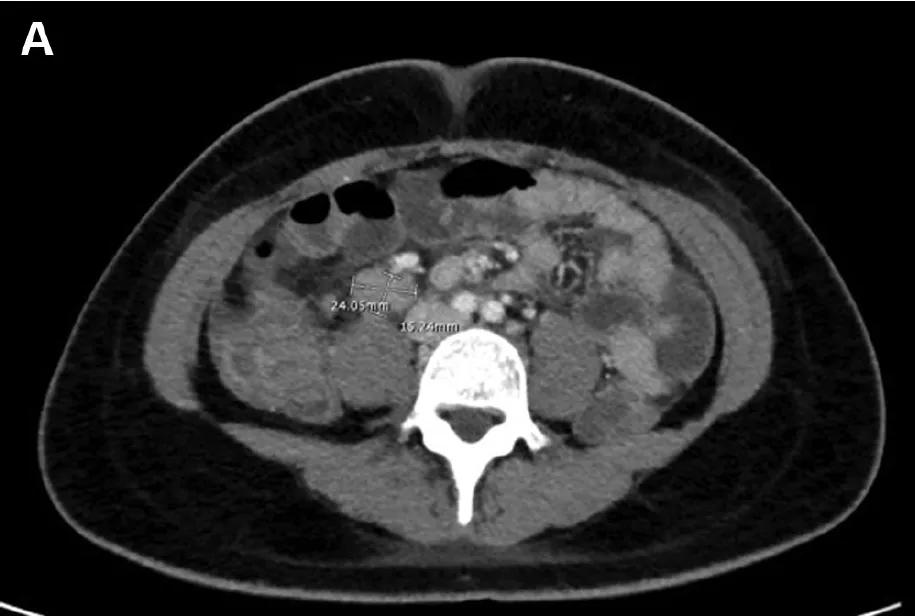

为10.5 g / dL,血小板计数为95 x 109 / L,碱性磷酸酶为401 IU / L,AST为 223 U / L,ALT 为117 U / L。 包括CT扫描在内的影像学检查显示回肠末端肠壁增厚,右结肠与肠系膜淋巴结肿大(图A)。